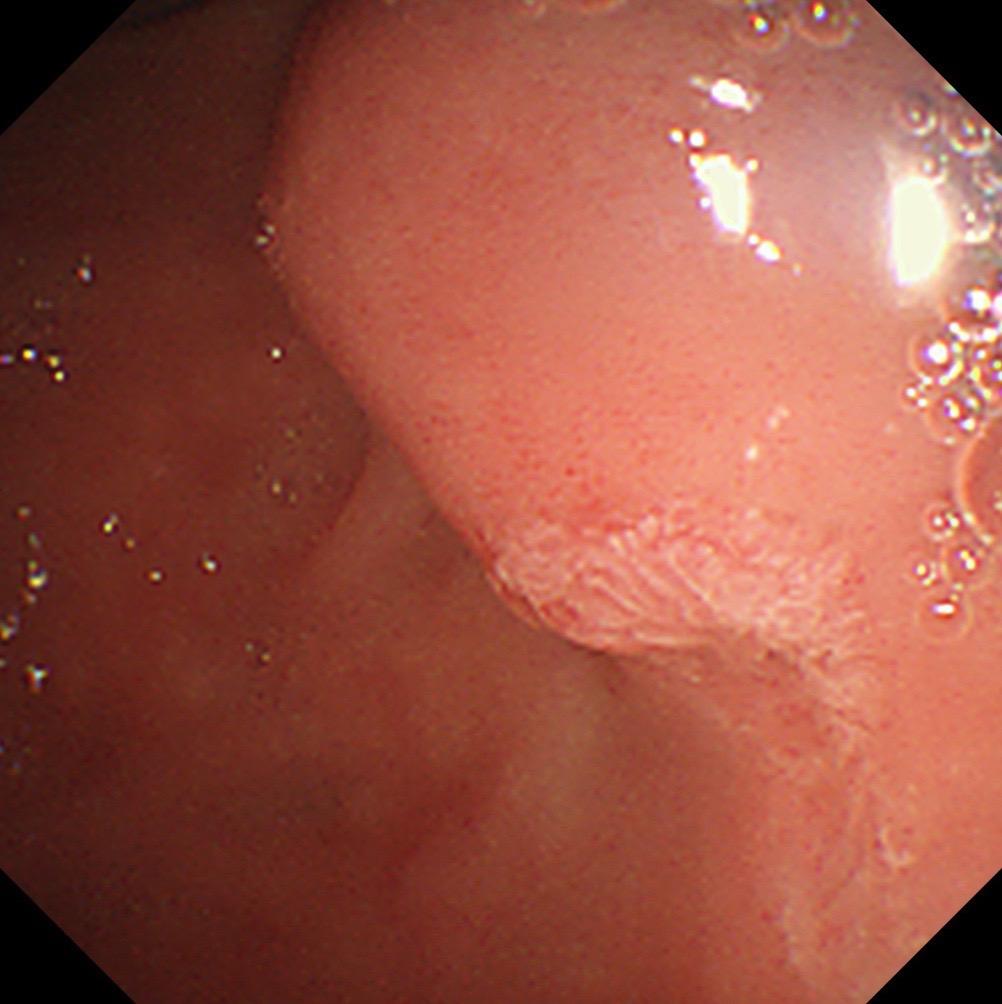

【精于术,简于形】 一例胃角间质瘤内镜下全层切除。 肿瘤虽小(2cm)...